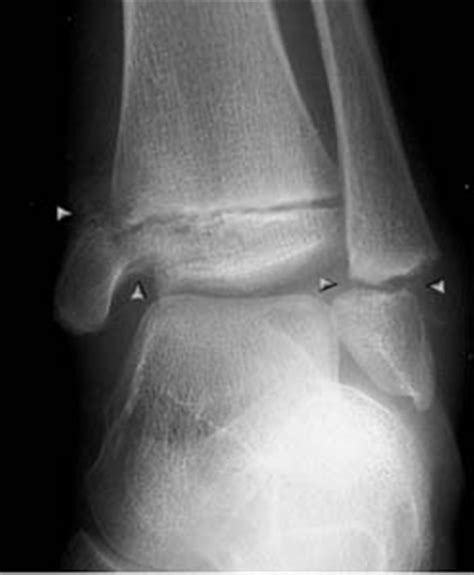

A lateral foot X ray can reveal a variety of conditions and abnormalities. Some of the most common findings include:

• Fractures: Fractures of the calcaneus, metatarsals, or other foot bones can be clearly seen in a lateral view.

• Arthritis: Joint space narrowing, bone spurs, and other signs of arthritis can be identified.

• Deformities: Conditions like flatfoot, high arches, or bunions can be evaluated.

• Foreign Bodies: Objects embedded in the foot, such as glass or metal, can be detected.

• Soft Tissue Abnormalities: Swelling, cysts, or other soft tissue issues can sometimes be seen.